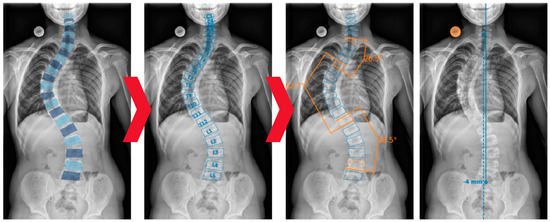

2.3. AI Model and Algorithms